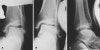

영상 검사

발목관절이나 거골하 관절의 불안정이 의심되면 varus & anterior stress x-ray 검사를 하고 반대편 발에서도 검사를 하여 비교하도록 합니다.

X-ray : Medial ankle instability